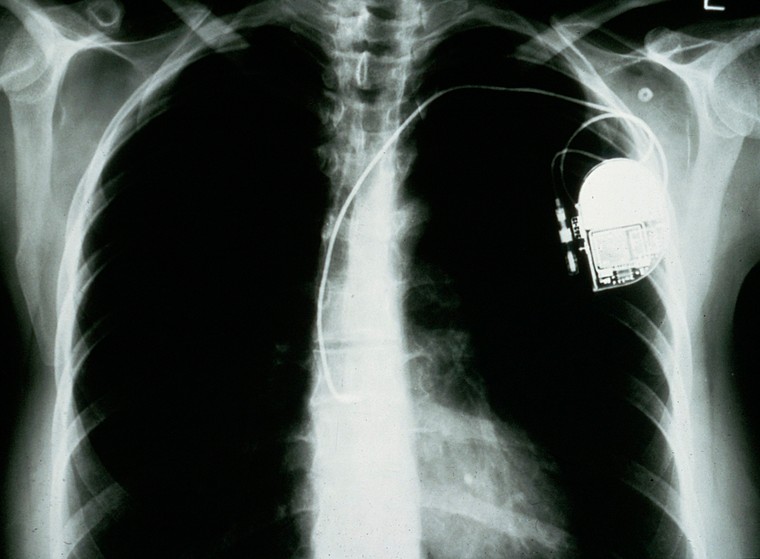

An X-ray image of a human chest with a pacemaker in situ, with a wire leading to the heart.

Pacemaker, atrial anti-tachycardia, Wellcome Collection